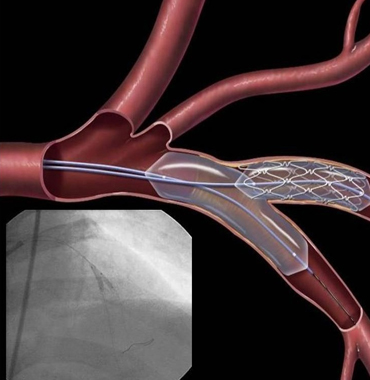

Interesting Cases